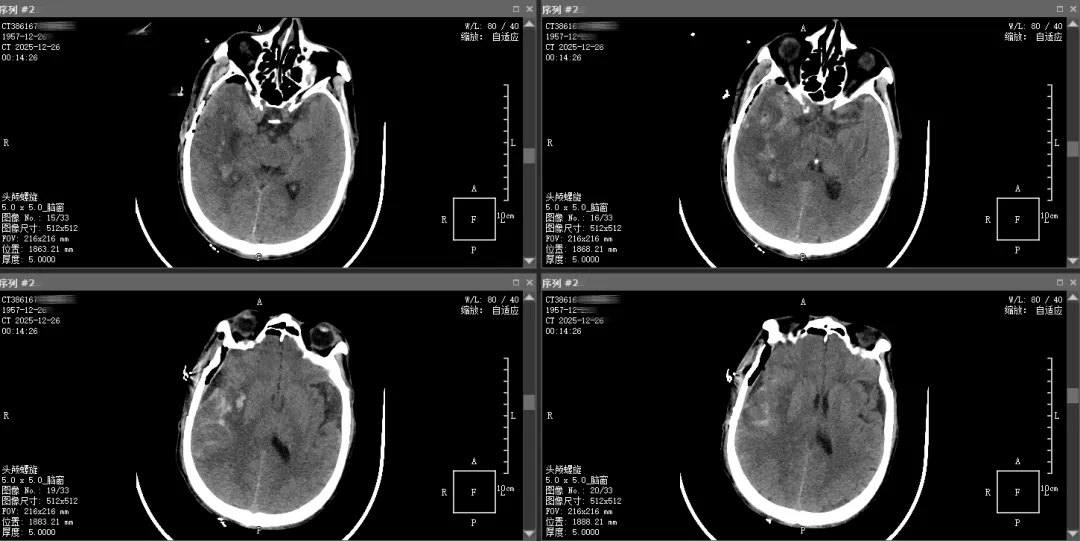

术后6小时复查头颅CT提示血肿完全清除,术区无积血残留,为恢复奠定基础。术后4天,患者完全清醒,顺利转回普通病房;术后15天,肢体功能完全恢复,可正常下床活动,符合痊愈出院标准。

▲术后复查头颅CT影像图